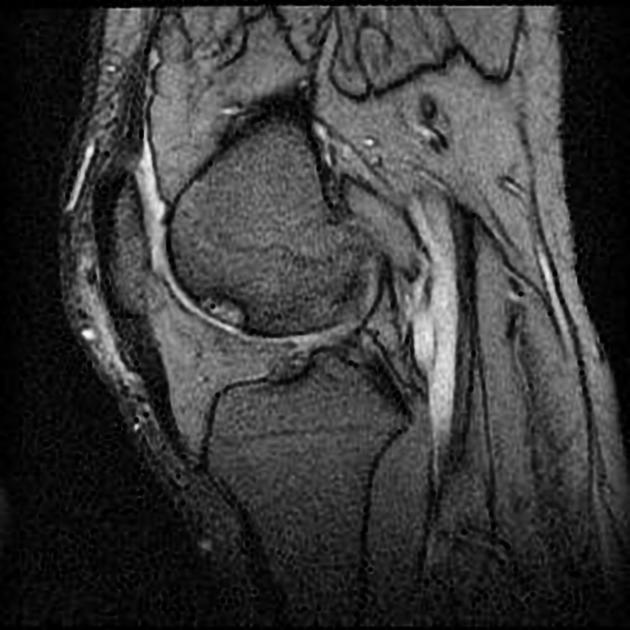

- Imaging: Ultrasound can reveal the doublecontour sign a clear indicator of crystal buildup. Xrays may appear normal in early stages.

Visual Aid

Medical journals often include that show the characteristic redness and swelling. Seeing these images can reassure you that youre not alone.